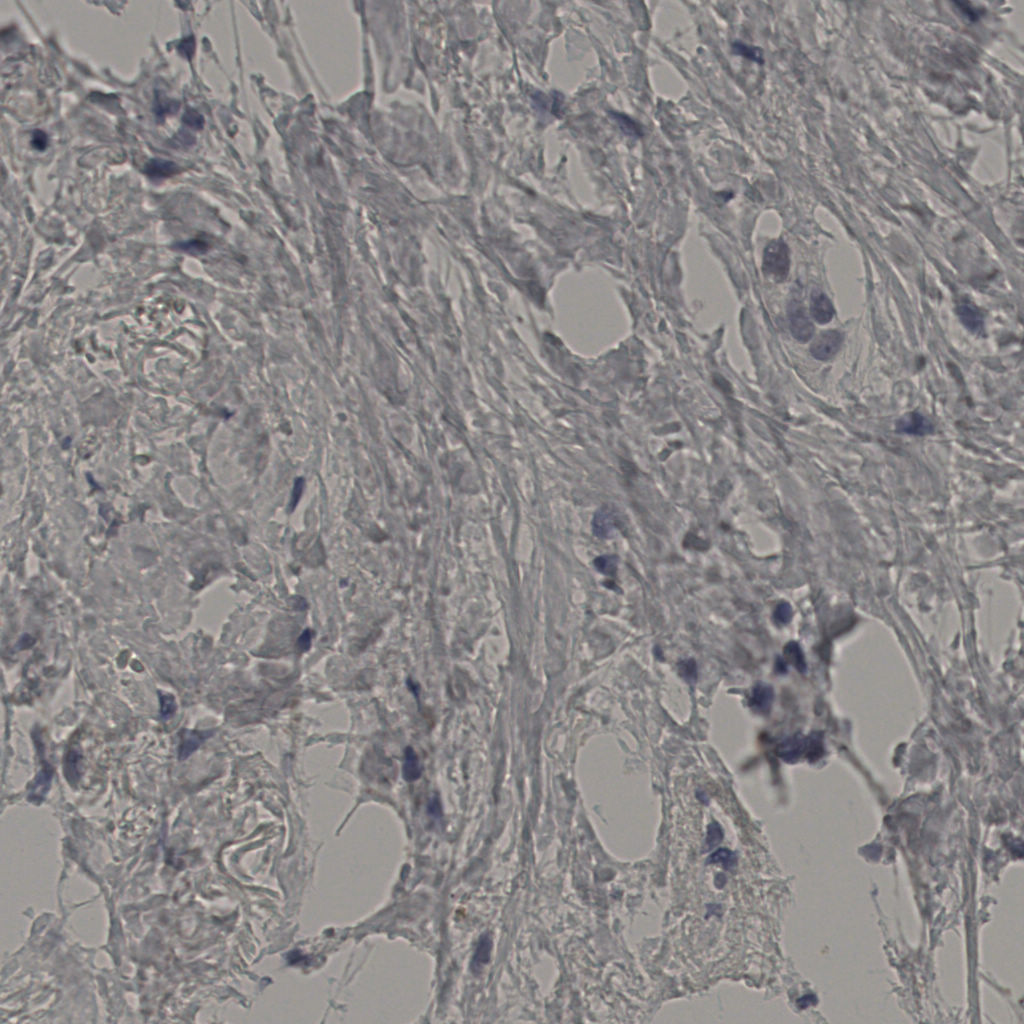

slice_43_26_x38528_y23296.png

slice_43_26_x3852...